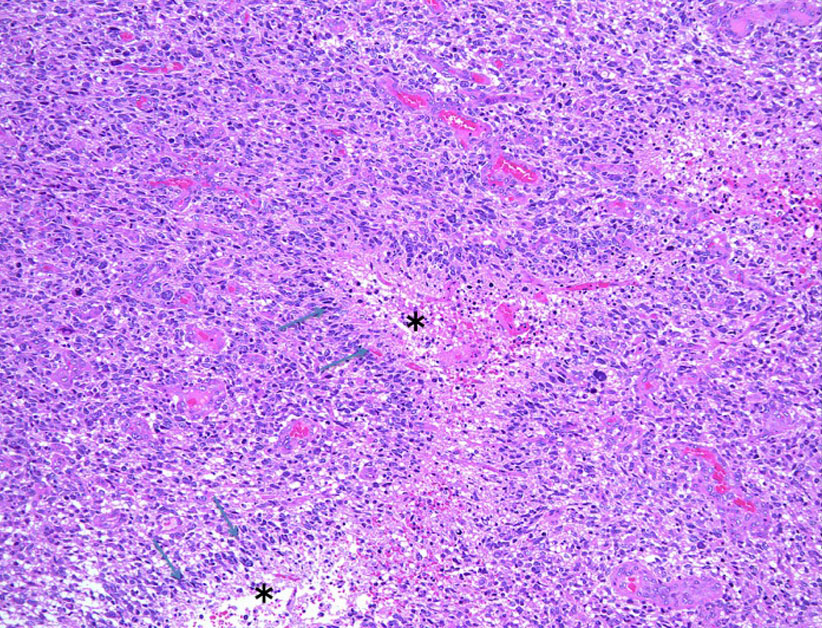

下の病理写真は,ある患者さんから私に送られたものです。20代で前頭葉の膠芽腫になってから21年経って生存しておられるということです。2度の開頭術と放射線治療と化学療法(複数回)を受けておられます。患者さんに病理診断が間違っているのではないかと返事をしたら,下にある画像を送ってくださいました。病理診断は,一見したところは多形膠芽腫 グリブラに間違いありませんでした。でも,ーーー

(下の画像は患者さんの許可を得て掲載させていただきました)

bizarre! 異様な細胞が混在しています。核多型が目立ち,多核巨細胞も混じる典型的な膠芽腫の像です。下の左の画像は血管内皮の肥厚 endovascular proliferationがあり,下の右のKi-67染色では核濃染像が多く核分裂能が高いことを示します。しかし,——

左のGFAP染色では一部の細胞が染色されません,右のHE染色では豊富な血管増殖の間に空砲 perinuclear halo を有した細胞増殖が見られます。さらに,–

腫瘍の部分像として明らかに乏突起膠腫が混在しています。また,どの部分をみても壊死 necrosisがありませんでした。

従って,この腫瘍の病理診断は,旧組織分類における退形成性乏突起星細胞腫 anaplastic oligoastrocytoma WHO grade III となります。2021年新分類では乏突起膠腫グレード3。